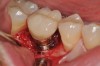

Fig 13. Radiograph depicting peri-implantitis.

Figure 13

Fig 14. Clear resin cement left on the implant abutment.

Figure 14

Fig 15. Implant abutment following cement removal.

Figure 15

Excess Cement Leading to Peri-implantitis

If all implant-supported crowns could be designed for screw retention, no discussion of excess cement would be necessary. However, screw retention is not always possible depending on the location of the access opening and because of the unesthetic appearance in anterior restorations or the mesial/distal angulation of the implant compromising the path of insertion (Figure 12). Residual cement left after crown cementation on implants can lead to peri-implant inflammation, peri-implantitis, and eventual loss of the implant (Figure 13 through Figure 15).25 The presence of lingering excess cement can encourage the development of bacterial colonization and peri-implantitis. Conversely, when too little cement is used, voids in the cement layer can occur and the prosthesis can become loose.26 The deeper the implant crown margin, the more difficult it is to remove excess cement.27

Radiopaque cements that contain zinc phosphate and zinc oxide (with and without eugenol) should be considered to help identify excess interproximal cement; however, this should be used secondarily to proper margin height and careful removal of cement during cementation. Resin cements lack the same opacity as zinc-containing cements and have been shown to be the most difficult to remove.28 Often in the process of removing this excess cement, the abutment surface becomes scratched and damaged, potentiating further plaque accumulation.29

Several modifications in abutment design and cementation have been suggested. Placing vent holes in the abutment during fabrication or leaving most of the screw-access chamber open for access has reduced the amount of cement that expresses out into the sulcus.26 It is also beneficial to extraorally express excess cement on an abutment replica prior to final crown seating to minimize complications. If retrievability is desired with cementable implant crowns, weaker cements (eg, zinc oxide eugenol) should be used first and progressively changed until the desired retention is achieved.